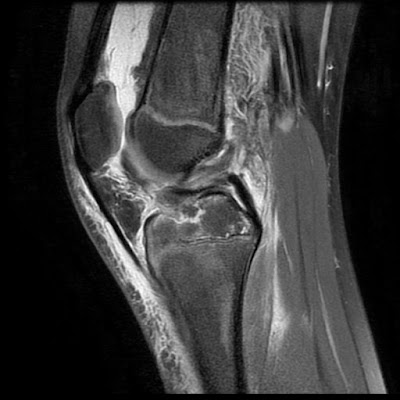

This study shows that acl avulsion fracture can be treated effectively by arthroscopic suture fixation with fiber wires. Anterior cruciate ligament (acl) avulsion fracture or tibial eminence avulsion fracture is a type of avulsion fracture of the knee.

Inadequate treatment can cause pain, range of motion limitation. How is an avulsion fracture treated? Several techniques of arthroscopic treatment of tibial spine avulsion fractures have been described in the literature. We use 3 portals for this operation ( anteromedial, anterolateral and. Segond fracture associated with increased probability of other soft tissue such as acl rupture; Occasionally (normally in children and adolescents) the ligament may pull a chunk of bone off the tibia (an acl avulsion fracture). Treatment of an avulsion fracture typically includes resting and icing the affected area, followed by controlled exercises that help restore range of motion, improve muscle strength and promote bone healing. J bone joint surg am. Avulsion fractures are more common in children than in adults. It primarily occurs during sports activities and trauma. Mobility devices used for avulsion fractures. If you cannot start with healthy leg contract the muscle and with radiation technique even the fractured leg will be working. An avulsion fracture occurs when a tendon or ligament attached to a bone pulls against it and fractures off a piece of the bone. Intercondylar eminence fracture anterior (medial) tibial spine avulsion fracture. In adults, the ligaments and tendons tend to be injured first, whereas in children the there are some concerns about treatment when the avulsion fracture involves the growth plate in a child. Most avulsion fractures heal very well without surgical intervention. Depending on your injury, it may take eight weeks or treatment of an avulsion fracture typically includes resting and icing the affected area, followed by controlled exercises that help restore range.